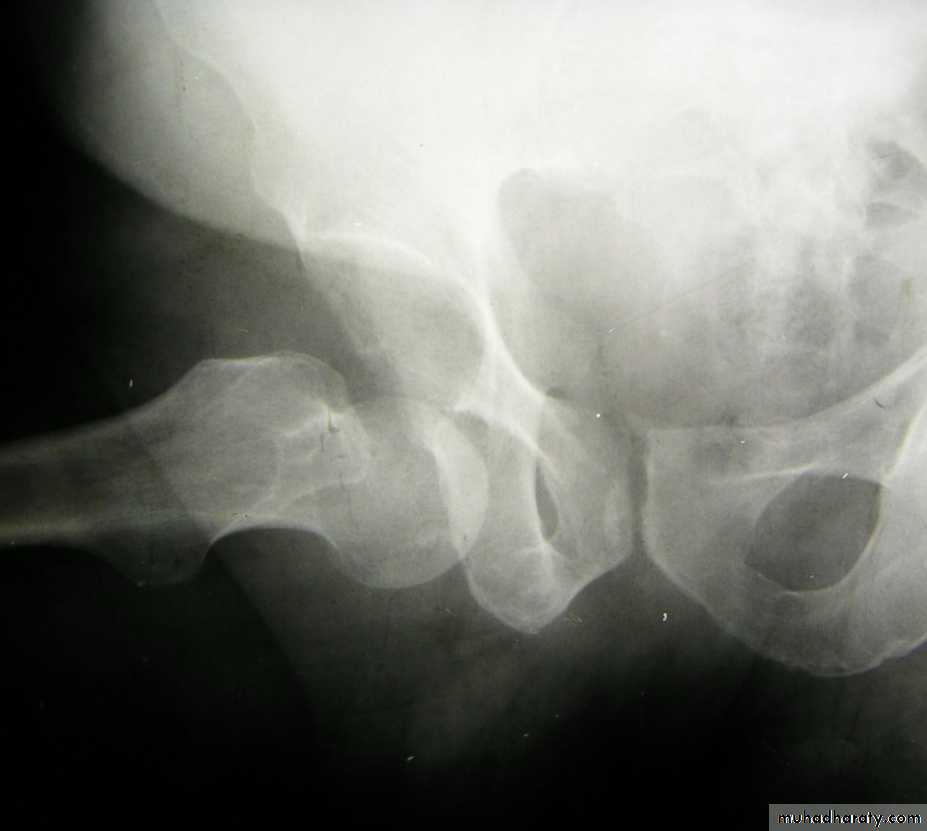

Pathological anatomy divided into:

Stable:Unstable are those where

a. posteriomedial cortex is shattered.b. poor contact between fracture segment.

Radiological examination

2 typesStable.

Unstable.